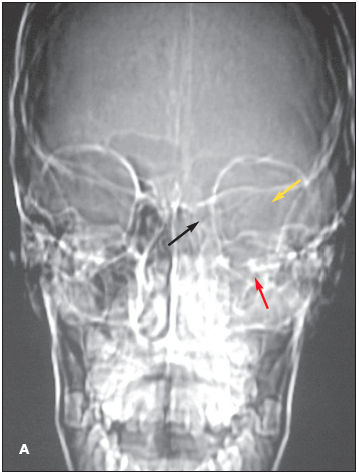

Intraorbital abscess: The radiographs demonstrate opacity of the ethmoid air cells on the left (A and B, blackarrows) with increased opacity of the left maxillary antrum, which is best seen on the frontal view (A, red arrow). The sphenoid and frontal sinuses are unremarkable. The increased density seen on the films results from the filling of the normally aerated sinuses with opaque material (in this case, mucus).

Close inspection also reveals increased density of the left orbit (A, yellow arrow). This density is attributable to edema.

Coronal (C) and axial (D) CT images confirm the radiographic findings of opacity of the ethmoid air cells (red arrows) and maxillary antrum (black arrow) caused by mucus and fluid. These images also define the extent of orbital edema and proptosis (yellow arrows).